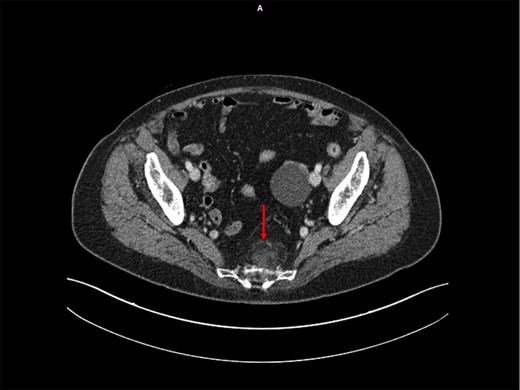

An asymptomatic 72-year-old woman with a history of hysterectomy without ovariectomy underwent a pelvic ultra-sound that revealed a cystic formation on the left ovary. Pelvic magnetic resonance (MR) confirmed the diagnosis of a left ovarian cyst and revealed a solid expansive mass in the presacral area that was ~6 cm in diameter, had a lobulated morphology, was strictly adherent to the sacral periosteum, was mainly adipose but exhibited an extremely non-homogeneous signal intensity (Fig. 1). The MR framework did not exclude the diagnosis of a malignant neoplasm such as a liposarcoma. The patient also underwent a contrast-enhanced CT scan that revealed the presence of an elongated formation of mainly adipose density (but with multiple areas of structural non-homogeneity) that was adherent to the presacral fascia (without bone infiltration) and exhibited a modest enhancement; the presence of multiple areas of structural non-homogeneity and modest enhancement precluded the exclusion of a malignant liposarcoma (Fig. 2). The risk that it was a malignant neoplasm contraindicated the execution of a CT-guided biopsy.

Abdominopelvic CT scan following injection of iodinated contrast agent—Presacral elongated formation of adipose density with multiple areas of structural not-homogeneity, with regular margins, adherent to the presacral fascia (but without bone infiltration) and with a modest enhancement after IV injection.